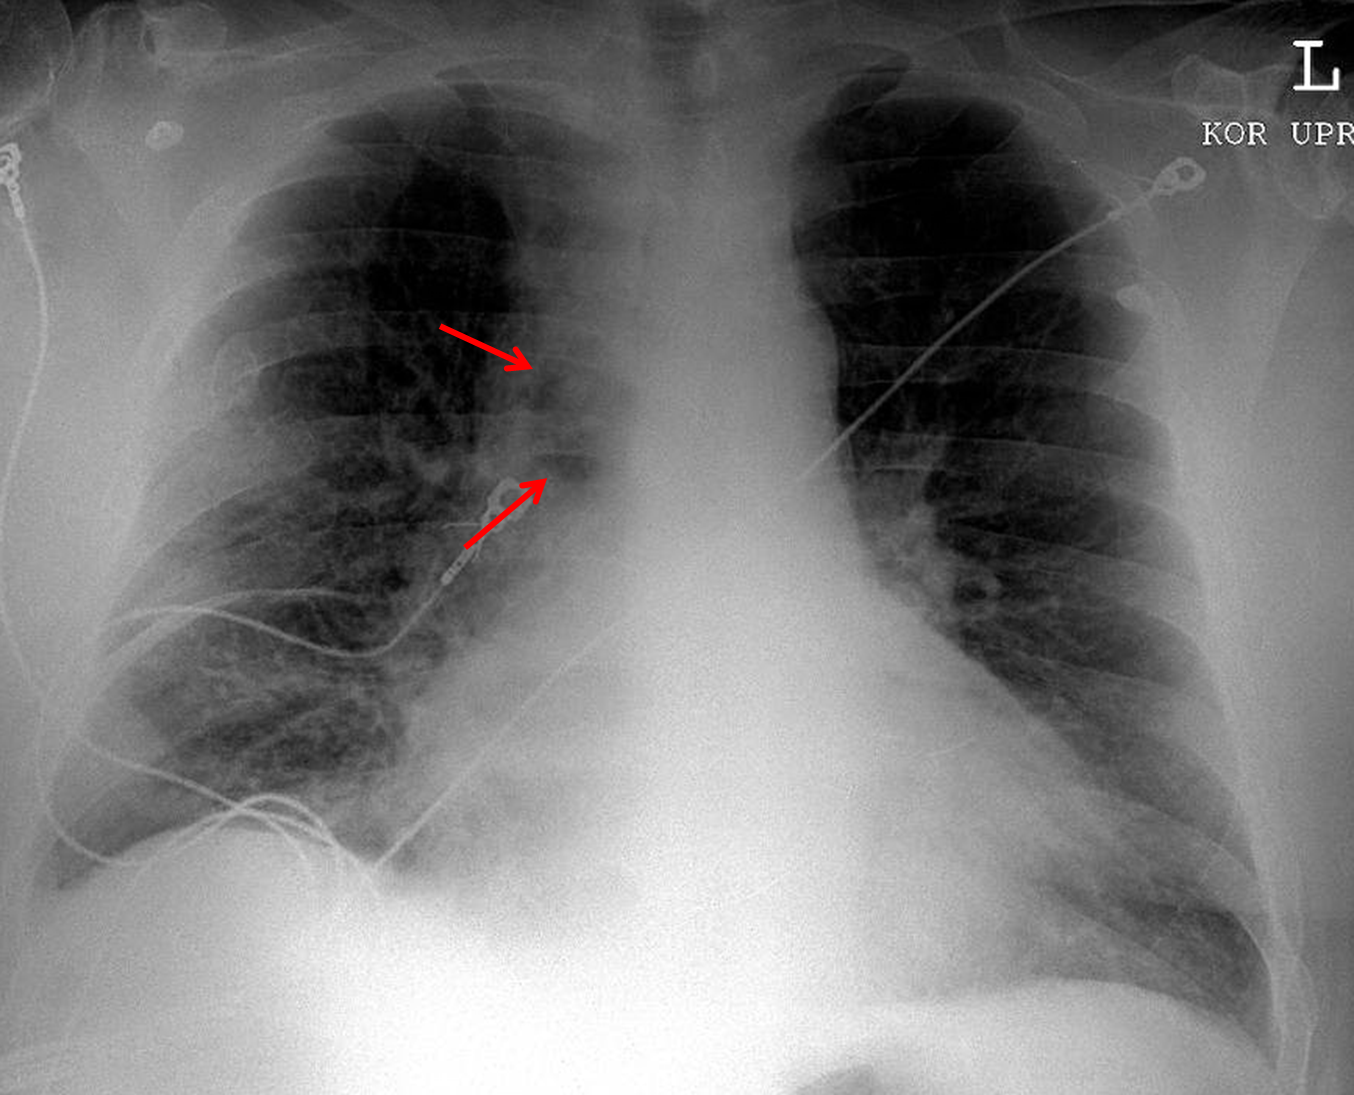

Age: 63

Sex: Male

Indication: Fever, dyspnea

Sample ReportWidening of the superior mediastinum with a rounded lucency along the right mediastinal margin, which findings raise particular concern for mediastinitis in the patient presenting with fever. Loculated mediastinal gas may relate to a necrotizing infection and/or communication with the trachea or esophagus. Recommend CT chest for further evaluation.

Patchy bibasilar airspace opacities are concerning for aspiration and/or pneumonia.

Small right pleural effusion.